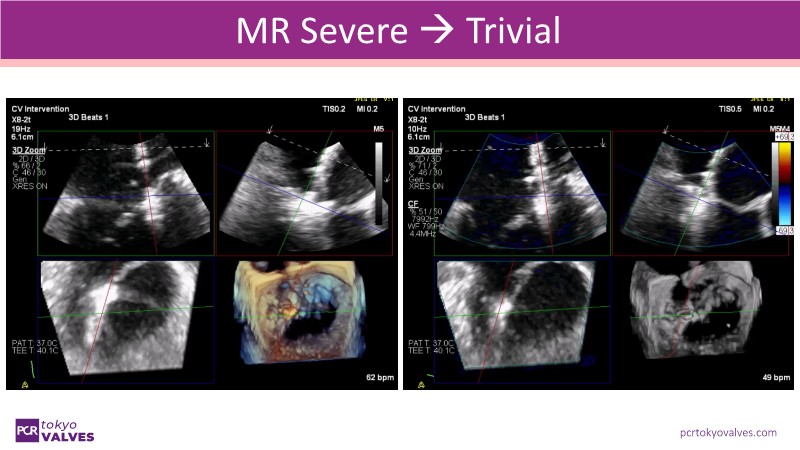

Explore the latest advancements in TEER therapy with this PCR Tokyo Valves 2025 session dedicated to MitraClip. Through expert-led case discussions, gain a deeper understanding of complex scenarios, including restricted posterior leaflet in functional mitral regurgitation, commissure lesion (A3P3), and MitraClip combined with Amulet.

This session also highlights key findings from the OCEAN study, shedding light on 1-year heart failure rehospitalisation outcomes with MitraClip. Additionally, discover how atrioventricular valve morphology impacts treatment strategies and how the four available clip sizes can be used to personalise and optimise TEER outcomes.